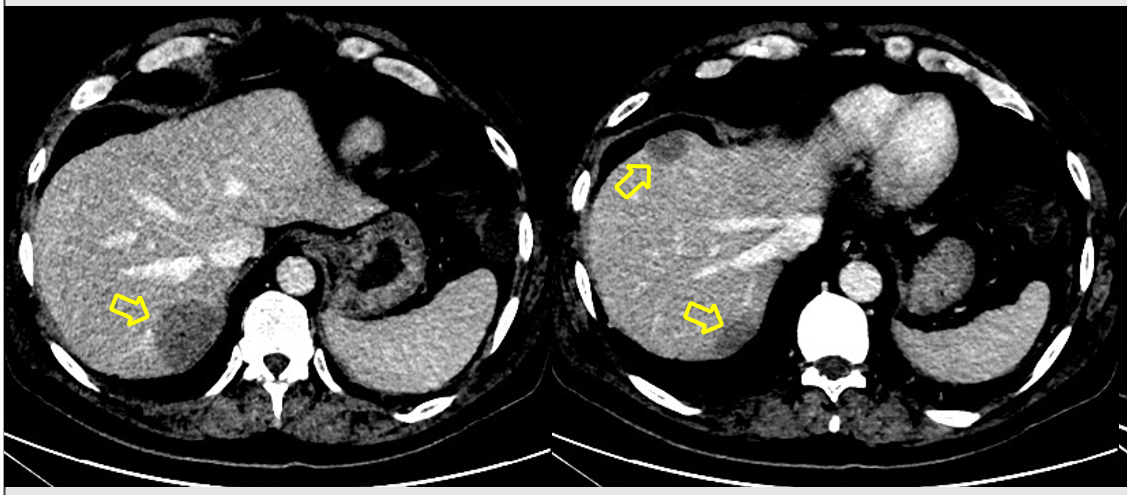

HALLAZGOS RADIOLÓGICOS